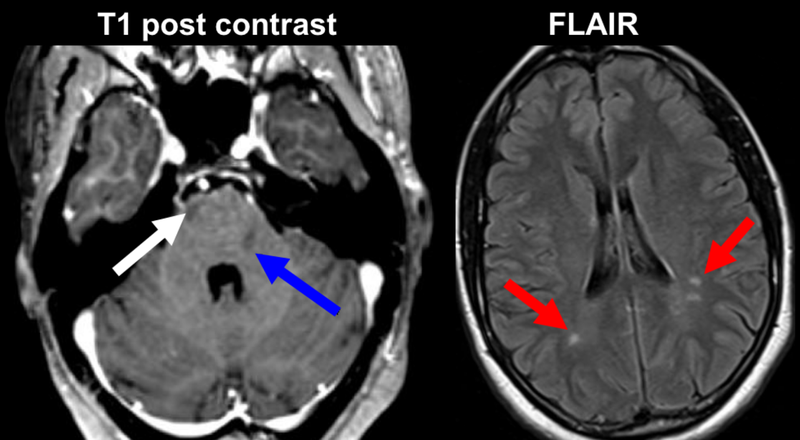

Tổn thương hoặc gián đoạn dẫn truyền trên dây thần kinh số VI ở bất kỳ vị trí nào dọc theo đường đi của nó cũng có thể dẫn đến mất chức năng. Liệt dây thần kinh số VI có những nhóm nguyên nhân khác nhau giữa trẻ em và người lớn.

Ở người trưởng thành, nguyên nhân gây liệt dây thần kinh số VI có thể do:

Người trưởng thành bị liệt dây thần kinh số VI có thể do một trong những nguyên nhân như đột quỵ não, tăng áp lực nội sọ, bệnh đa xơ cứng, giang mai, bại liệt, viêm tai xương chũm, covid-19,...